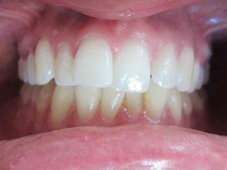

Présentation cas clinique :

Avant traitement

Après traitement